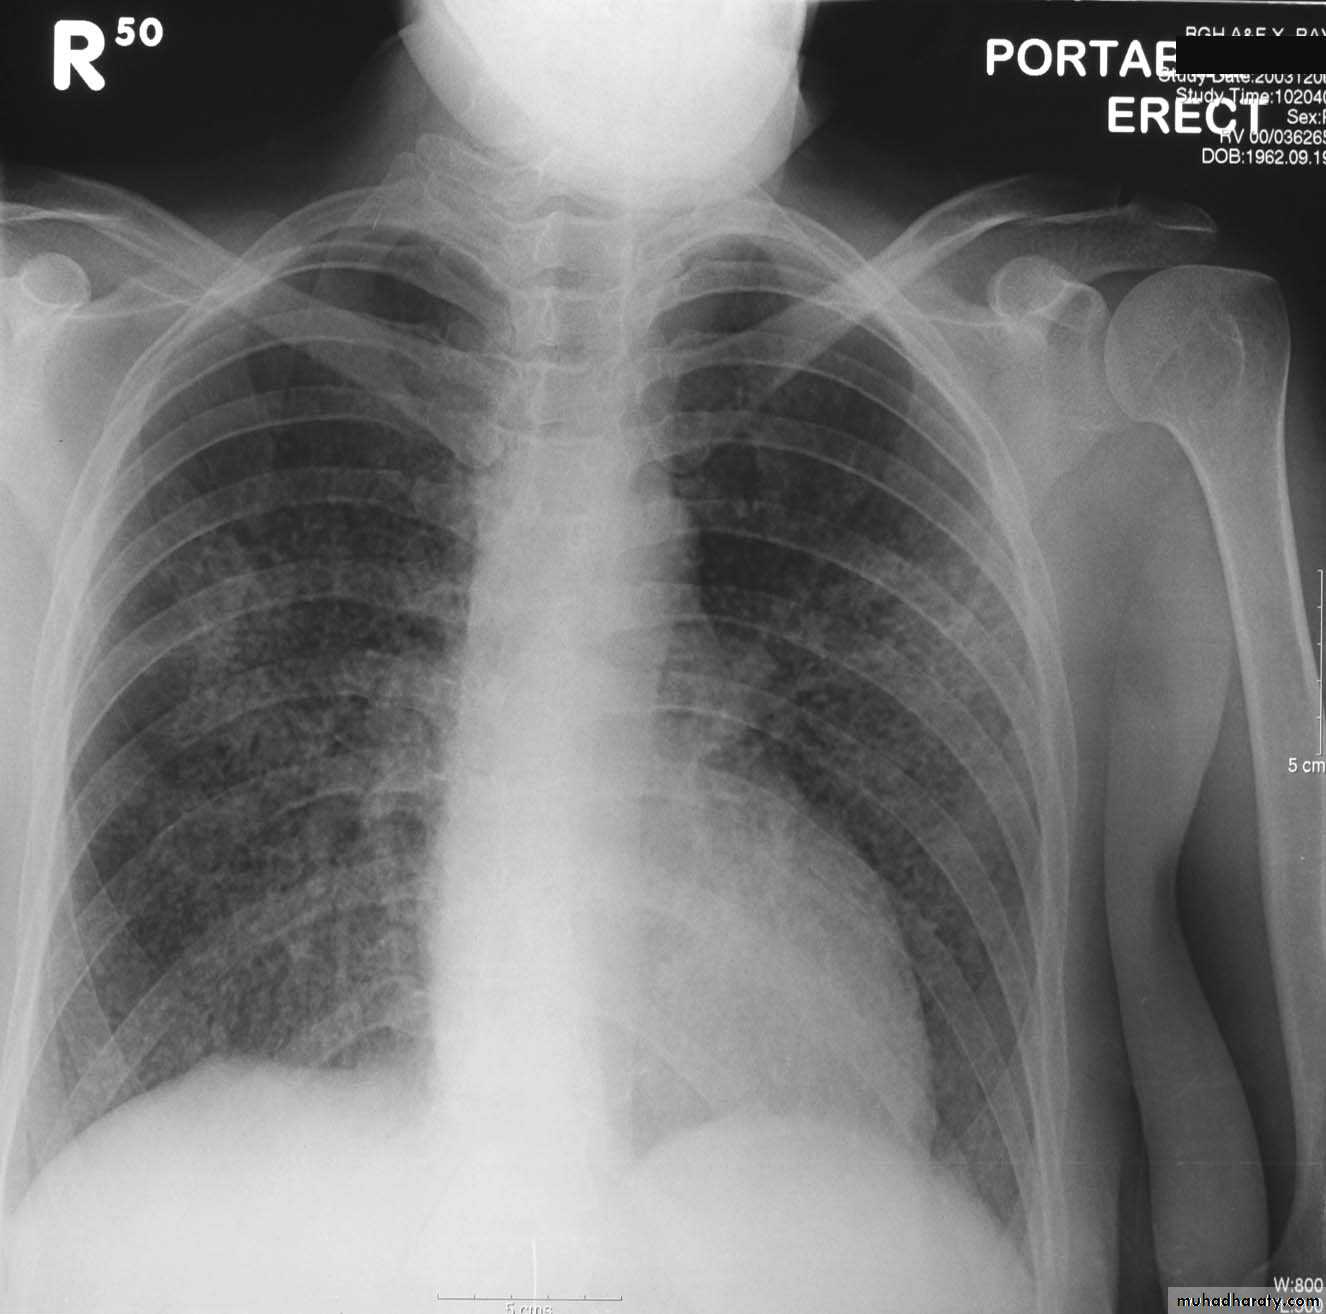

Chest X-ray:

Used In:

A -Preoperatively. B- Pre-employment .

C - Patient complains from respiratory symptoms.

D - Patient complains from cardiovascular symptoms.

Routine Examination includes

P-A view , Other supplementary views are done according to the case. So all Patients admitted to hospital should have P-A X-ray In standing erect view in complete inspiration